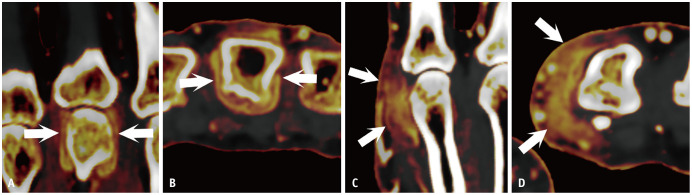

Fig. 5. Comparison of typical capsular synovitis between RA and PsA on dual-energy CT iodine maps. A, B: Coronal (A) and axial (B) images of the hand in a 75-year-old female with RA show enhancement in the 3rd MCP joint (arrows). C, D: Coronal (C) and axial (D) images of the hand in a 64-year-old female with PsA shows capsular synovitis with periarticular inflammation in the 2nd MCP joint (arrows). RA = rheumatoid arthritis, PsA = psoriatic arthritis, MCP = metacarpophalangeal.

A dynamic MRI study showed that contrast enhancement persists longer in RA compared with PsA at 15 minutes post-contrast [23]. This persistence in enhancement may reflect histopathologic changes, such as the tendency for contrast media to remain within the proliferated synovium in RA. Although conventional contrast-enhanced MRI alone is insufficient to distinguish synovitis between these two types of arthritis, the typical joint capsular synovitis in PsA is accompanied by periarticular inflammation and appears more dramatic than in RA (Figs. 4, 5).

Several studies have emphasized that periarticular inflammation is a key imaging feature for differentiating PsA from RA [24,25,26]. If the enthesis is the primary inflammatory target in PsA, capsular enthesitis may develop prior to the onset of capsular synovitis, and such cases may occasionally be encountered (Fig. 6).